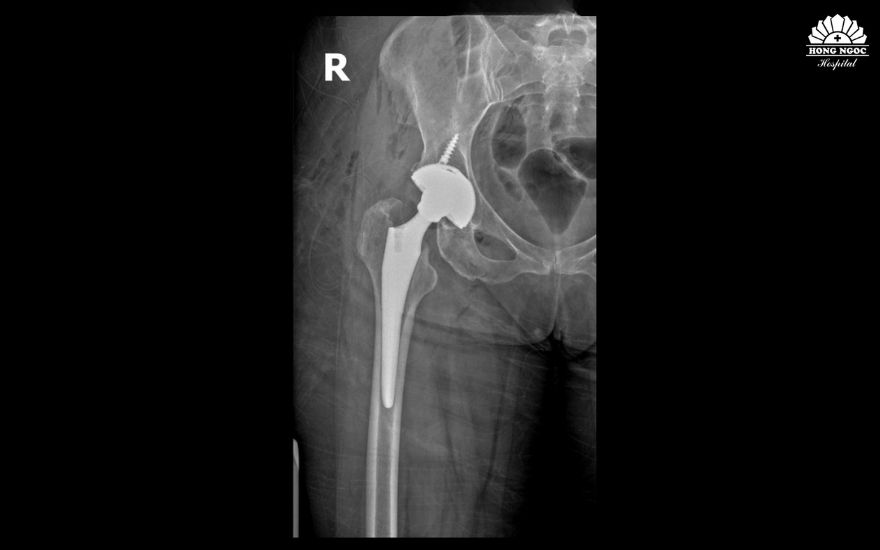

.jpg)

Phim chụp khớp háng của bệnh nhân Ronit sau phẫu thuật.